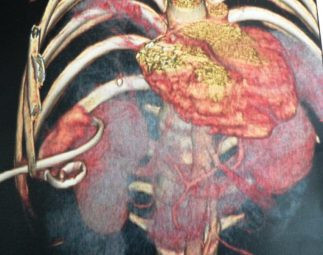

Drenaje percutáneo de absceso hepático

Envíado por Dr. Carlos Miguel Zavaleta Consuegra